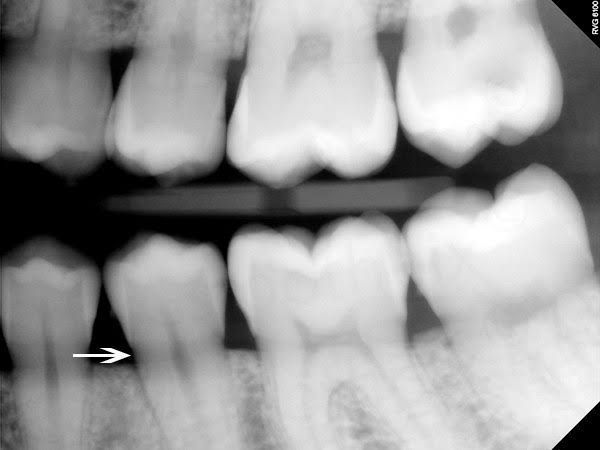

Cervical burnout

Cervical burnout appears as a radiolucent band around the necks of teeth and is more pronounced at the proximal edges. The X-ray photons overpenetrate or burn out the thinner tooth edge and create the radiolucent area that mimics cervical caries